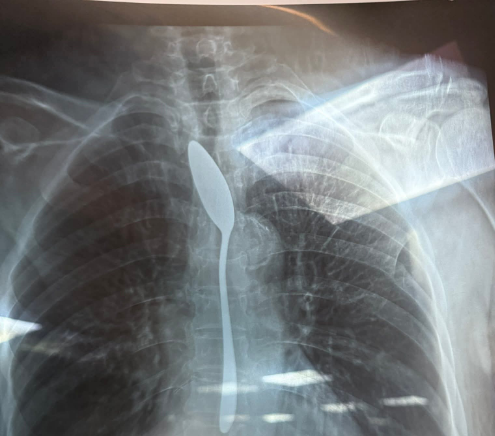

نجح فريق طبى بقسم الجراحة العامة بمستشفى شبين الكوم التعليمى بمحافظة المنوفية، من استخراج ملعقة من بطن مريضة مسنة.

من جانبه، أكد الدكتور أحمد شهاب طبيب بقسم الجراحة العامة بمستشفى شبين الكوم التعليمى بمحافظة المنوفية، على وصول حالة مسنة لطوارئ مستشفى شبين الكوم التعليمي تبلغ من العمر 70 سنة ترافقها نجلتها تؤكد معاناة والدتها بسبب قيامها ببلع ملعقة صغيرة .

على الفور تم إجراء إشاعه للسيدة وتبين وجود ملعقة، على الفور تم تجهيز السيدة وتم إجراء الجراحة لها داخل غرفة العمليات في وقت قياسي من 5 لـ 7 دقايق، وتم استخراج الملعقة.